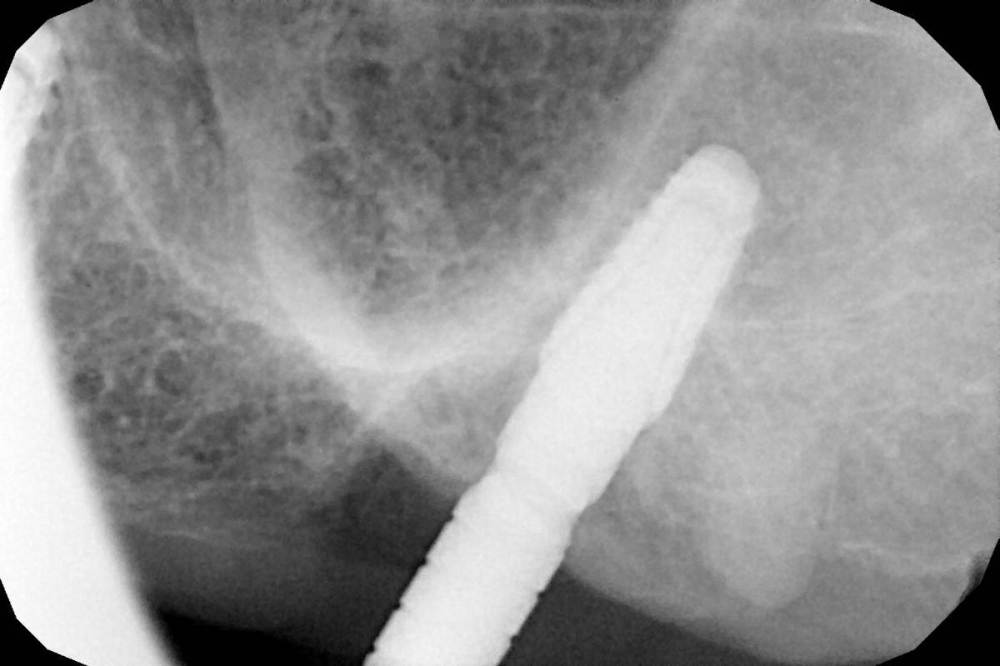

Дмитрий Л. Опубликовано 17 января, 2022 Поделиться Опубликовано 17 января, 2022 Не корешок? Ссылка на комментарий

Женька Опубликовано 2 июня, 2022 Автор Поделиться Опубликовано 2 июня, 2022 Вот как то так... вроде не так уж критично близко, как считаете? При проверке на 30 н/см2 имплант 2.7 провернулся и положительный "ой" тест Ссылка на комментарий

kramer Опубликовано 3 июня, 2022 Поделиться Опубликовано 3 июня, 2022 А есть снимок? Ссылка на комментарий

Женька Опубликовано 3 июня, 2022 Автор Поделиться Опубликовано 3 июня, 2022 @kramer отправил на КТ прицел совершенно никакой информации не дал Ссылка на комментарий